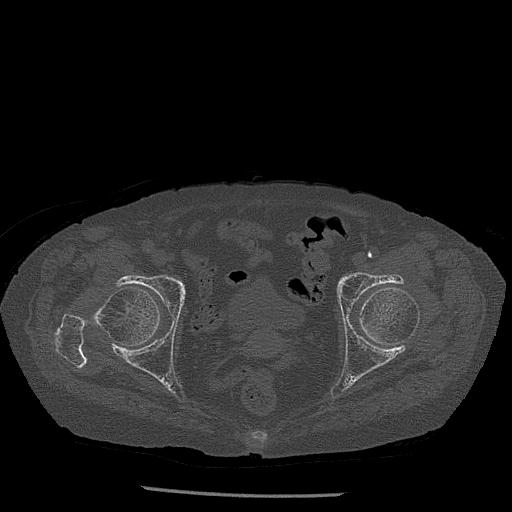

100703 1/27 両股正面+軸 1/29 両股正面+軸 94歳女性 パンソンロン